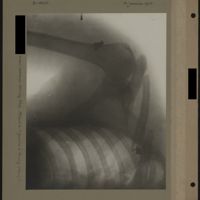

0007 - Page 3 - [Radiographies du bras]0007 - Page 3 - [Radiographies du bras]